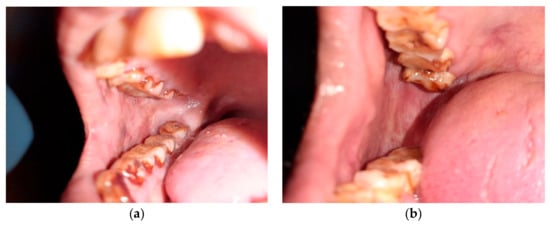

2.1. Clinical Examination: (Figure 3)

Thorough intra-oral and extra-oral examination were performed and a clinical diagnosis for each lesion was made [23].

Extra-oral examination:

Face and head were assessed to find abnormal findings such as symmetry, swelling or discoloration

Neck was palpated to assess major lymph nodes for any lumps, swelling, and tenderness

Intra oral examination:

Examination was done with the help of mouth mirror and probe. Lips, palate, tongue, floor of mouth, buccal mucosa, labial mucosa, and fauces were checked for discoloration, texture, keratinization, swelling, consistency or any other abnormality, such as fibrous bands.

Lesions were diagnosed as tobacco pouch keratosis when the mucosa appeared gray or gray-white and almost translucent in localized areas contacting the tobacco. The surface of the mucosa appears white and is granular or wrinkled and in some cases, a folded character may be seen. The stretched mucosa appears fissured or rippled, and a “pouch” is usually present. This white tobacco pouch may become leathery or nodular in long-term, heavy users, and the lesion is usually asymptomatic [7]. The oral tissue can be white or may appear wrinkled and, in rare instances, may elicit folding. When the mucosa is stretched, it may resemble fissures, and it may present with a “pouch”. In patients with a history of consuming tobacco for a prolonged duration, the oral mucosal pouch may elicit changes including leathery characteristics, and the lesion is usually asymptomatic.

Smoker’s palate was diagnosed when palatal mucosa was seen as diffusely grayish or whitish and erythematous. Oral lesions may exhibit papules with a central erythematous punctate. Such lesions may form on both the soft and the hard palate, especially in long-term tobacco smokers.

The areas with clinical manifestations are those that are in constant exposure to the heat generated during smoke inhalation.

“Reverse smoking” has been shown to elicit severe manifestations, including lesions of the erythroleukoplakic variety. Such cases are frequently noted in long-term tobacco smokers [7].

Leukoplakia was inferred in those cases which presented with white lesions which were not scrapable and were demarcated. The surface of the lesion may appear to have multiple fissures and may elicit a cracked, mud-like feel on palpation [7].

The diagnosis of, was rendered if the clinical presentation included either palpable fibrotic bands or at the least exhibited an opaque, blanched appearance. The diagnosis can also be rendered in cases wherein the patient complains of a sensation of irritation/burning following the consumption of spicy foods. The burning sensation may be accompanied by vesicular and ulcerative changes in the oral mucosa, which may progress to oral mucosal stiffness which may culminate in reduced mouth opening [7].

Figure 3. Methodology for clinical examination, Participants information, Consent & uniform instructions.

Healthcare 10 01507 g003